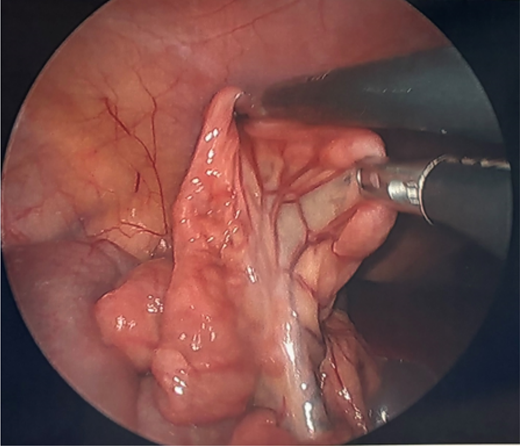

Image depicting the small bowel and its mesentery with mildly prominent lymph nodes.